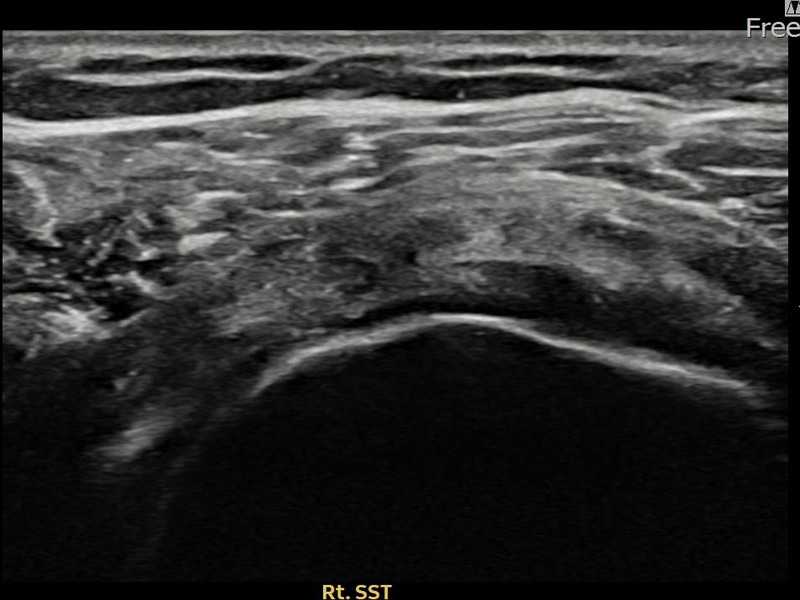

최ㅇㅇ님 · 우측 극상근건 관절면측 파열 진행형

우측 어깨 파열이 진행된 상태로 수술 없이 치료를 원해 내원하셨습니다. 다각도 초음파 평가 후 축소봉합술을 시행하여 힘줄 구조가 안정화되었습니다.

상세 보기 →